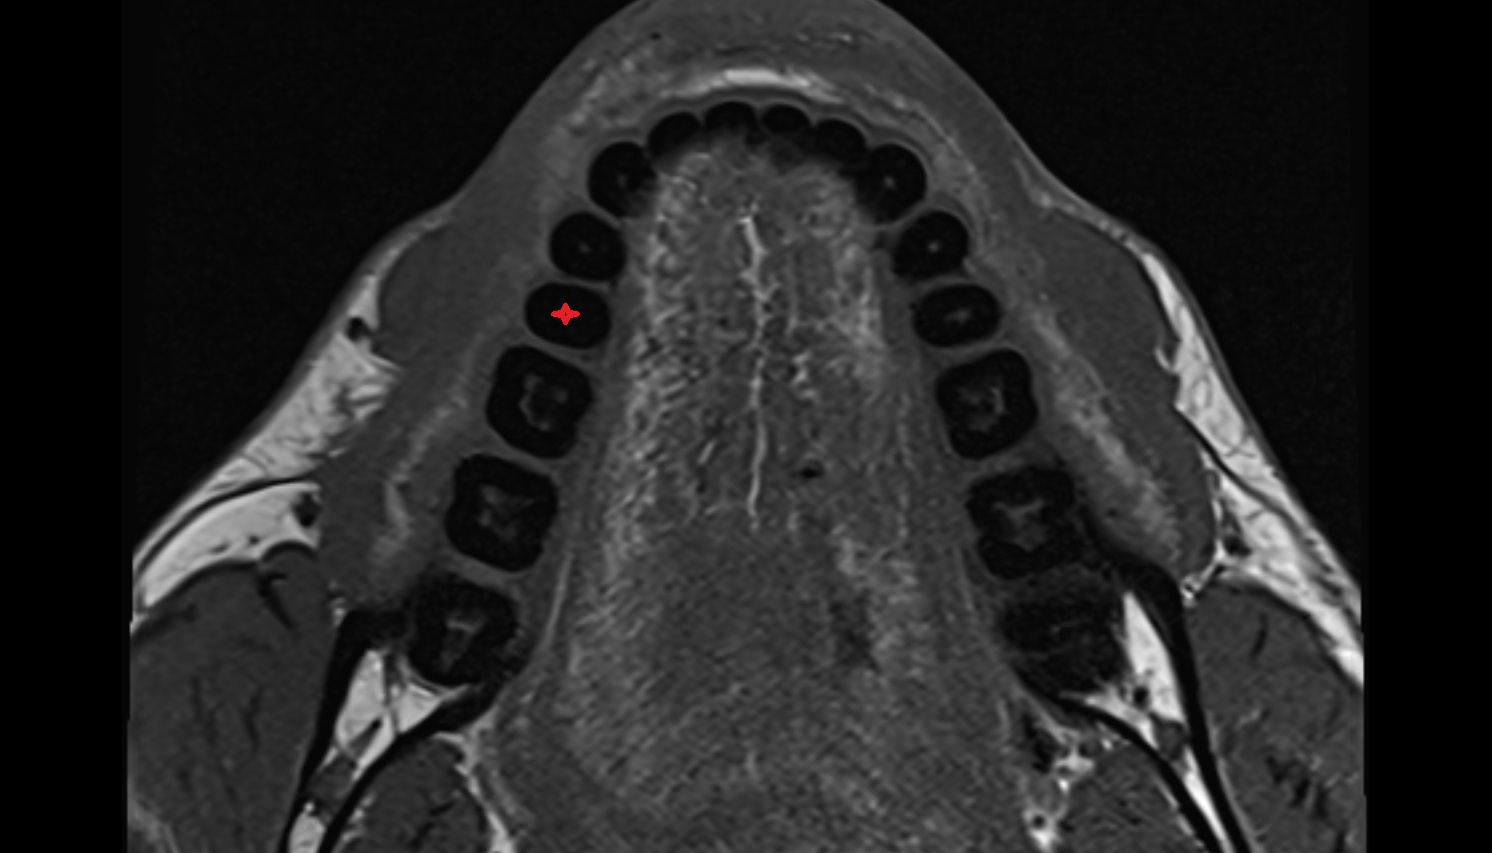

- Central inferior incisor tooth

- Central superior incisor tooth

- Inferior canine tooth

- Lateral inferior incisor tooth

- Lateral superior incisor tooth

- superior canine tooth

- Superior first molar tooth

- Superior first premolar tooth

- Superior second molar tooth

- Superior second premolar tooth

- Superior third molar tooth

- Inferior first premolar tooth

- Inferior second molar tooth

- Inferior second premolar tooth

- Inferior third molar tooth

- Root of lower molar tooth

- Root of upper molar tooth

- Root canal of upper molar tooth

- Dental pulp of upper molar tooth

- Enamel of lower molar tooth

- Enamel of upper molar tooth

- Enamel of upper incisor tooth

- Enamel of lower incisor tooth

- Enamel of lower premolar tooth

- Dental pulp of lower molar tooth

- Alveolar process of maxilla

- Superior dental plexus